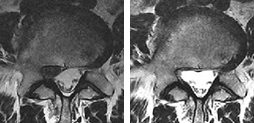

Starpskriemeļu diska trūces rezorbcijas metode

Kā notiek rezorbcija?

Samazinoties starpskriemeļu diska trūcei, pacients sāk justies atvieglojums un akūts sāpju sindroms pamazām pārvēršas nelielā diskomfortā un pēc tam pazūd pavisam. Sāpju simptomu izzušanas ātrums ir 1-3 mēneši, bet atsevišķos gadījumos tas var aizņemt ilgāku laiku, atkarībā no organisma īpatnībām un trūces veida.

Šie divi faktori ietekmē rezorbcijas kvalitāti un veiksmi. Pat ja rezorbcija notiek pati no sevis (mazāk nekā 40% iespējamība), literatūrā ir aprakstīts vidējais termiņš 12-18 mēneši, atkarībā no diska bojājuma pakāpes un organisma spējas atjaunoties.